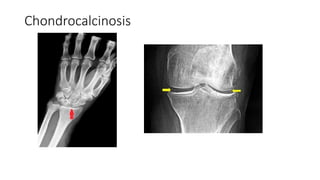

โ€ข x-ray knee shows โ€“ chondrocalcinosis, multiple loose bodies,

โ€ข X-ray hand โ€“ triangular ligament calcification.

โ€ข X-Ray Knee โ†’ B/L chondrocalcinosis +, osteophyte

โ€ข X-Ray hands โ†’ Right triangular / calcification+

โ€ข X-Ray Pelvis: Chondrocalcinosis at B/L inferomedial margin of hip joint

Chondrocalcinosis